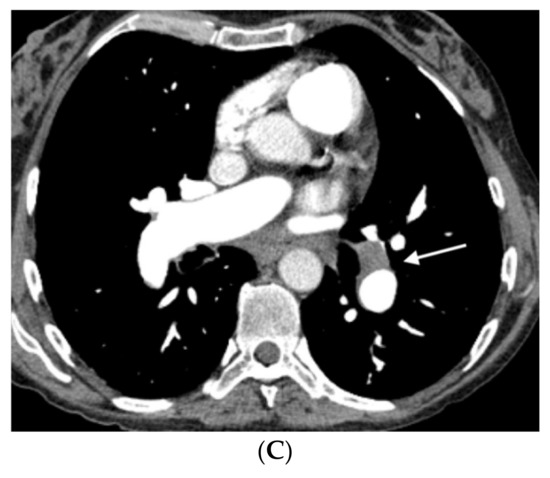

Figure 4.

Fifty-five-year-old woman with sporadic PVOD histologically diagnosed after double lung transplantation. The patient had three typical MDCT findings and in situ thrombus in the left main pulmonary artery (normal ventilation-perfusion scintigraphy excluded CTEPH). (A) Dilation of the pulmonary artery (PA) trunk with thrombus in situ in the left main pulmonary artery (arrows); (B) ground-glass centrilobular nodules in both upper lobes (arrows) and septal lines (short arrows); (C) left hilar adenopathy (arrow). PA: pulmonary artery.